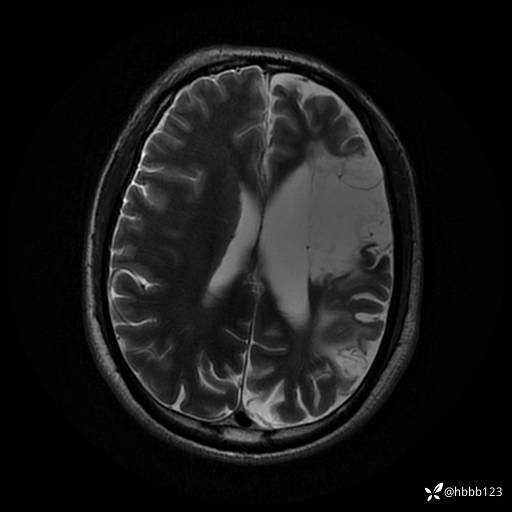

患者男,43岁。

简要病史:癫痫患者复诊,昨日发作5-6次,建议住院进一步治疗。

入院完善脑癫痫组合序列:

T2: